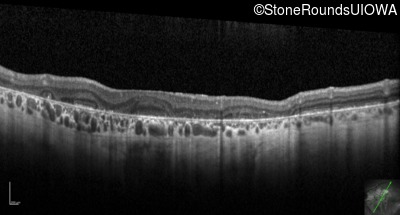

Optical Coherence Tomography - Left - 20/200

Exemplar / OCT Stack